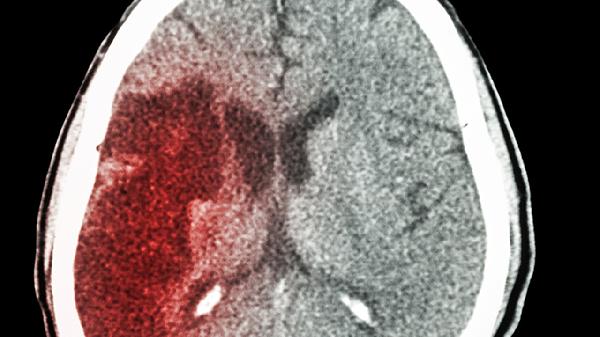

石榴泡酒对脑梗并无治疗作用,脑梗患者应避免饮酒并及时就医接受规范治疗。

石榴本身富含多酚类物质如花青素和鞣花酸,这些成分在体外研究中显示出抗氧化特性,可能帮助减少自由基对血管内皮的损伤。石榴中的钾元素有助于维持电解质平衡,对血压调控存在潜在益处。但浸泡过程会使酒精溶解部分营养素,长期存放易导致维生素C等活性物质降解。酒精本身会刺激血管收缩、增加血液黏稠度,反而可能加重脑部缺血风险。脑梗患者饮用含酒精饮品可能干扰抗血小板或抗凝药物疗效,甚至诱发血压波动。

脑梗的规范治疗需根据发病机制采取针对性措施。缺血性脑梗应在一线城市医院卒中中心开展静脉溶栓,使用阿替普酶注射液等药物恢复血流。对于动脉狭窄导致的梗死,可遵医嘱服用硫酸氢氯吡格雷片联合阿托伐他汀钙片进行二级预防。若存在心房颤动等心源性栓塞因素,需长期口服华法林钠片抗凝治疗。康复期可在医师指导下进行认知功能训练,同时控制每日钠盐摄入量低于5克。建议每周保持150分钟中等强度有氧运动,如太极拳或健步走,并定期监测血脂、血糖等指标。